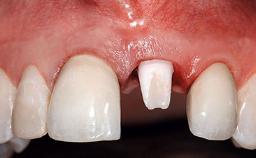

Replacement of an Upper Right Central Incisor with Root Resorption: Ridge Preservation, Delayed Placement of an NC Bone Level Roxolid Implant

A 32-year-old female Caucasian patient with a compromised maxillary right central incisor was referred to us by a general dentist. Her chief complaints were discomfort and mobility of tooth 11 with unsatisfactory esthetics due to discoloration. The patient reported a previous trauma, some years earlier, as the origin of pathology on the afflicted tooth. Anamnesis was negative for any other dental or periodontal pathology in the remaining dentition. The patient did not take any medication and reported to be a light smoker (5–10 cigs/day). She had high esthetic expectations of her treatment. The extraoral examination revealed a high smile line with full exposure of her maxillary teeth and surrounding soft tissue in the area between the second premolars.

Patient's Esthetic Expectations Low Medium High

Lip Line No exposure of papillae Exposure of papillae Full exposure of mucosa margin